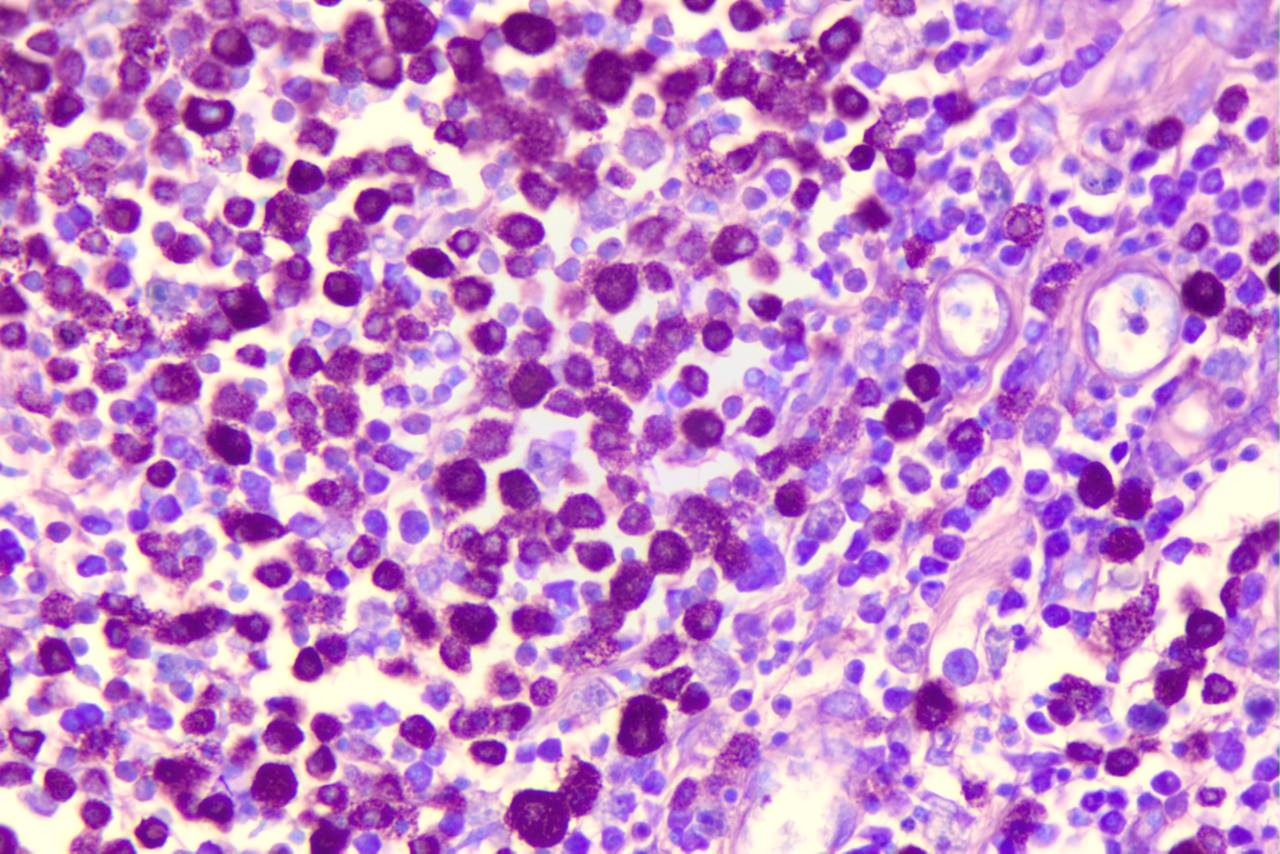

AT: Azul de Toluidina

Geralmente empregada em suspeitas de mastocitoma pouco diferênciados, visto que acentua a granulação intracitoplasmática em magenta, quando presentes. Embora também possa ser utilizado em testes de lignina.